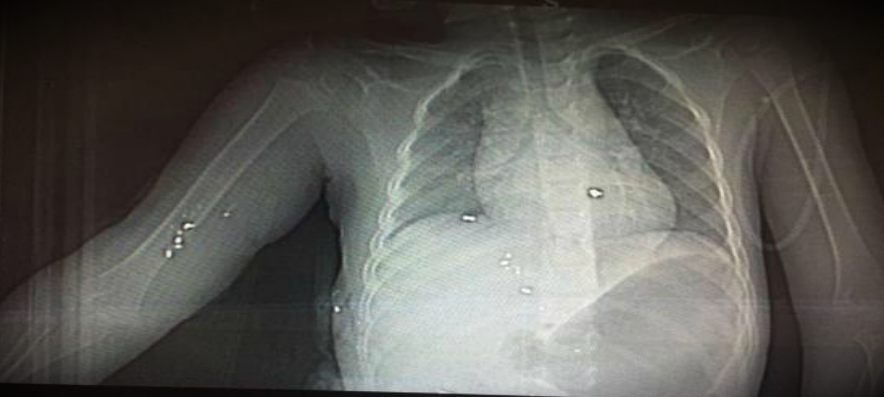

Los rayos X proporcionados por la familia muestran varios fragmentos de proyectil que permanecieron en el torso del niño hasta el momento de su muerte

X-ray of the bullet fragments which penetrated the 3 years old Sajaad who died today after 2 months of suffering.Was shot by #Saudi security pic.twitter.com/Ldy1XurFw9